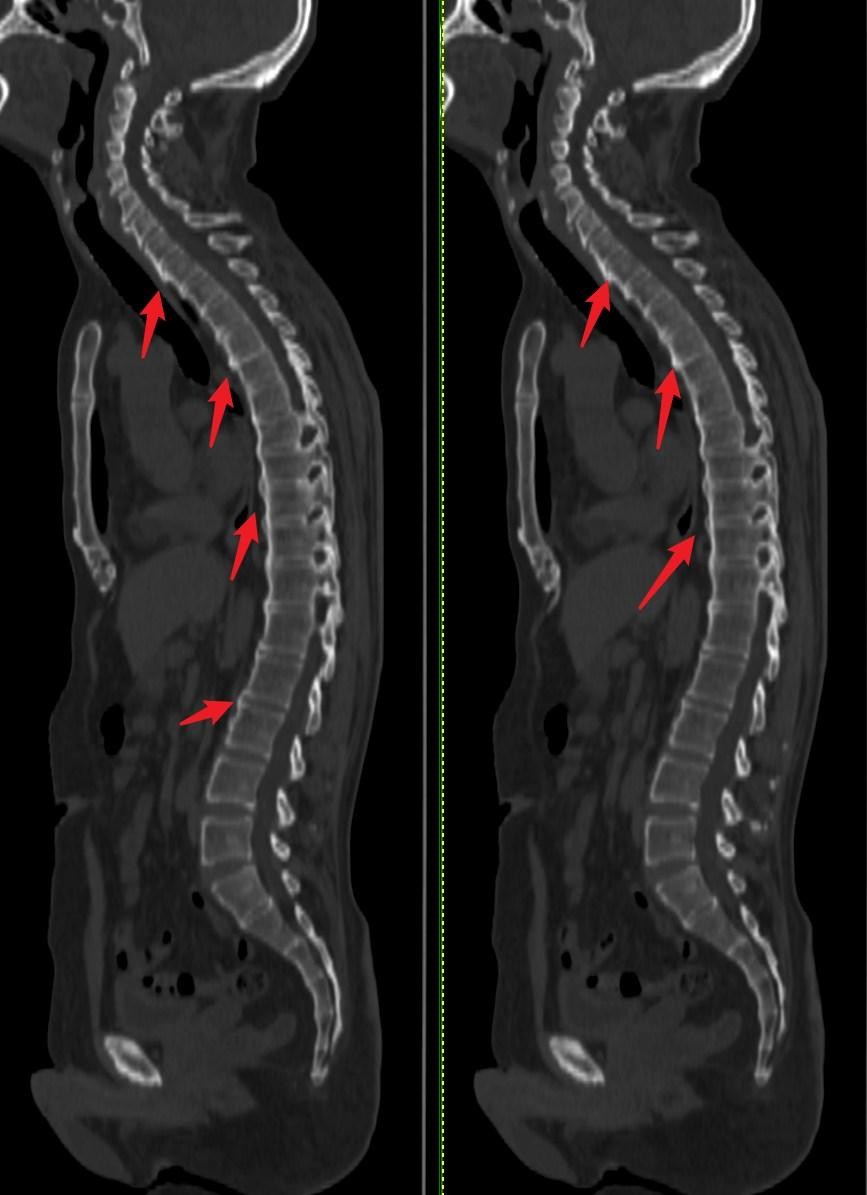

图4:程度严重的强直性脊柱炎↓

强直性脊柱炎是一种具有漫长病程的慢性进行性炎性病变,其治疗难度较大,会对患者的身心健康造成严重影响,给患者带来痛苦。强直性脊柱炎是指肌腱,韧带和关节囊等负责与骨关节部位的非特异性炎症,纤维化以致骨化回本病的基本病变,骶髂关节是本病最早累及的部位,病理表现为滑膜炎软骨变性破坏,软骨下骨板破坏以及炎症细胞的浸润等。